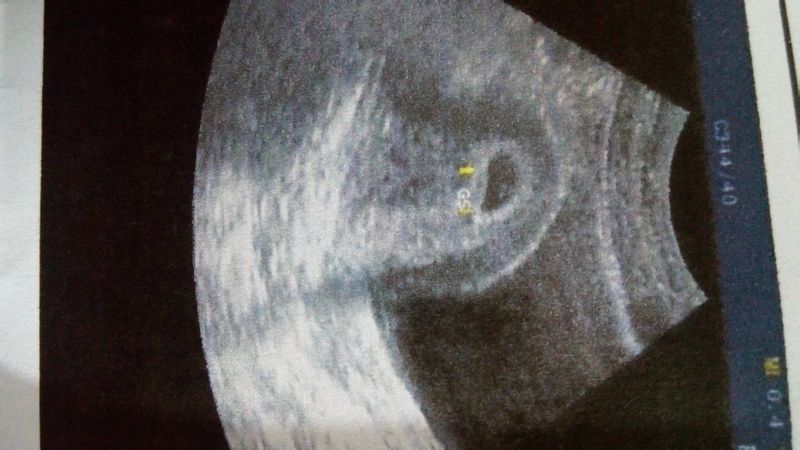

早早孕58天,请看图,谢谢! 点击展开 匿名用户 2015-02-10 23:04 为您推荐: 其他回答 一般在怀孕两个月左右能看见原始的胎牙和胎心波动,这个情况建议 你过一周左右复查 cn#BfGBBpkBua 2015-02-11 10:36 相关问题 早早孕试纸怎么看图 好担心,这几天总是睡不好觉,因为早早孕检测显示弱阳性,怕自己真的怀孕了怎么办!很愁,该怎么办呢 末次4月28日,21号早早孕测出怀孕,23日去医院验孕,孕酮35 32,HCG58 81,医生说HCG偏低,要我等一周再去验,有一样的宝妈吗?